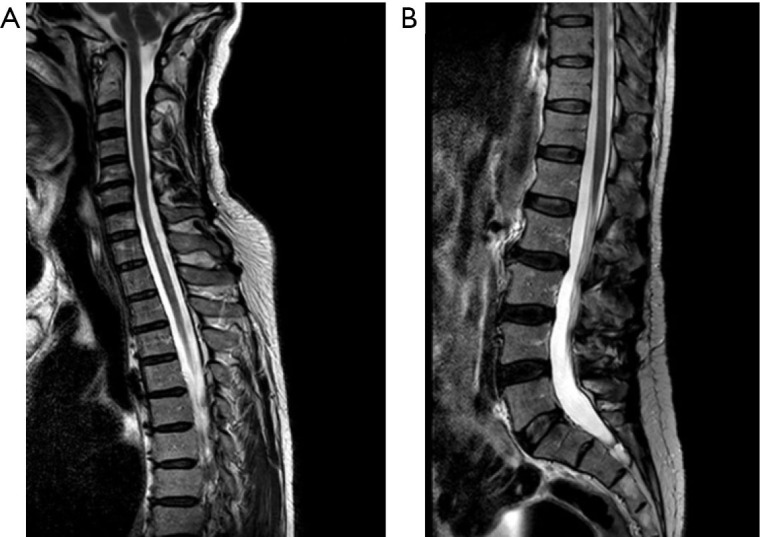

Case description: A 58-year-old Caucasian man was admitted to the Emergency Department (ED) with low back pain and walking inability. He had an unsteady gait, paraesthesia of the lower limbs and pain in the left lumbar area of the spine. He previously manifested repeated episodes of Raynaud's phenomenon. The neurological examination revealed pyramidal signs with asymmetric and progressive paraparesis associated with hypoesthesia and bladder dysfunction. A spine magnetic resonance imaging (MRI) revealed the presence of a long extensive cervico-dorsal myelitis. Among laboratory analyses, serum immunometric examinations came back positive for anti-RNP (272 U/mL) and anti-SSA (20 U/mL) antibodies, whereas a recombinant immunofluorescence assay revealed the presence of immunoglobulin G (IgG) antibodies against AQP4. Consequently, he was treated with high-doses of corticosteroids, with progressive resolution of symptoms. To date, his last cervico-dorsal spine MRI showed negative results.